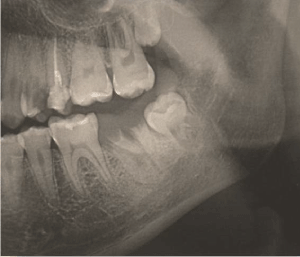

A healthy 17 year old female patient showed up at the Surgery Clinic of Federal University of Alfenas (UNIFAL-MG) Surgery Clinic. She had a Dentist referral to extract the tooth 37- left lower second molar, which had no possibility of restoration due to its huge crown destruction (Figure 1).

Fourteen days later, the transplanted tooth was in good condition. In the 34th day, continued root formation was observed (Figure 9 and Figure 10). After 4 months and 24 days, the transplanted tooth continued to be healthy as well as the gums around it. Also, the patient showed good oral hygiene. By using a radiographic exam, the continued root formation was seen (Figure 11).

Figures 11: Radiograph of the autotransplanted tooth 4 months and 24 days later.